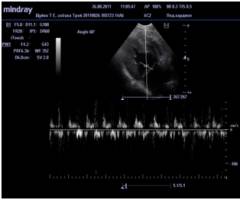

Эхокардиография или УЗИ сердца – позволяет выявить:

- Нарушения в створках аортального клапана;

- Дрожание створок митрального клапана;

- Увеличение левого желудочка.

Доплерография – на экране видно, как кровь просачивается через отверстие в аортальном клапане обратно в левый желудочек.

Трансторакальная ЭхоКГ (УЗИ сердца через грудную клетку) может выявить:

- увеличение левого желудочка и утолщение его стенок

- увеличение левого предсердия

- мембрану под клапаном

- валик над клапаном в аорте

- неполное смыкание створок

- количество створок

- суженное отверстие клапана

Чреспищеводная ЭхоКГ – метод, при котором датчик вводится в пищевод, близкий к сердцу, что позволяет точно измерить площадь отверстия в аортальном клапане.

Доплеровское исследование – разновидность УЗИ сердца, позволяющая:

- увидеть направление кровотока

- измерить скорость потока

- определить объем крови, проходящей через аортальный клапан

- выявить сужение над клапаном

- обнаружить недостаточность аортального клапана – неполное закрытие его створок